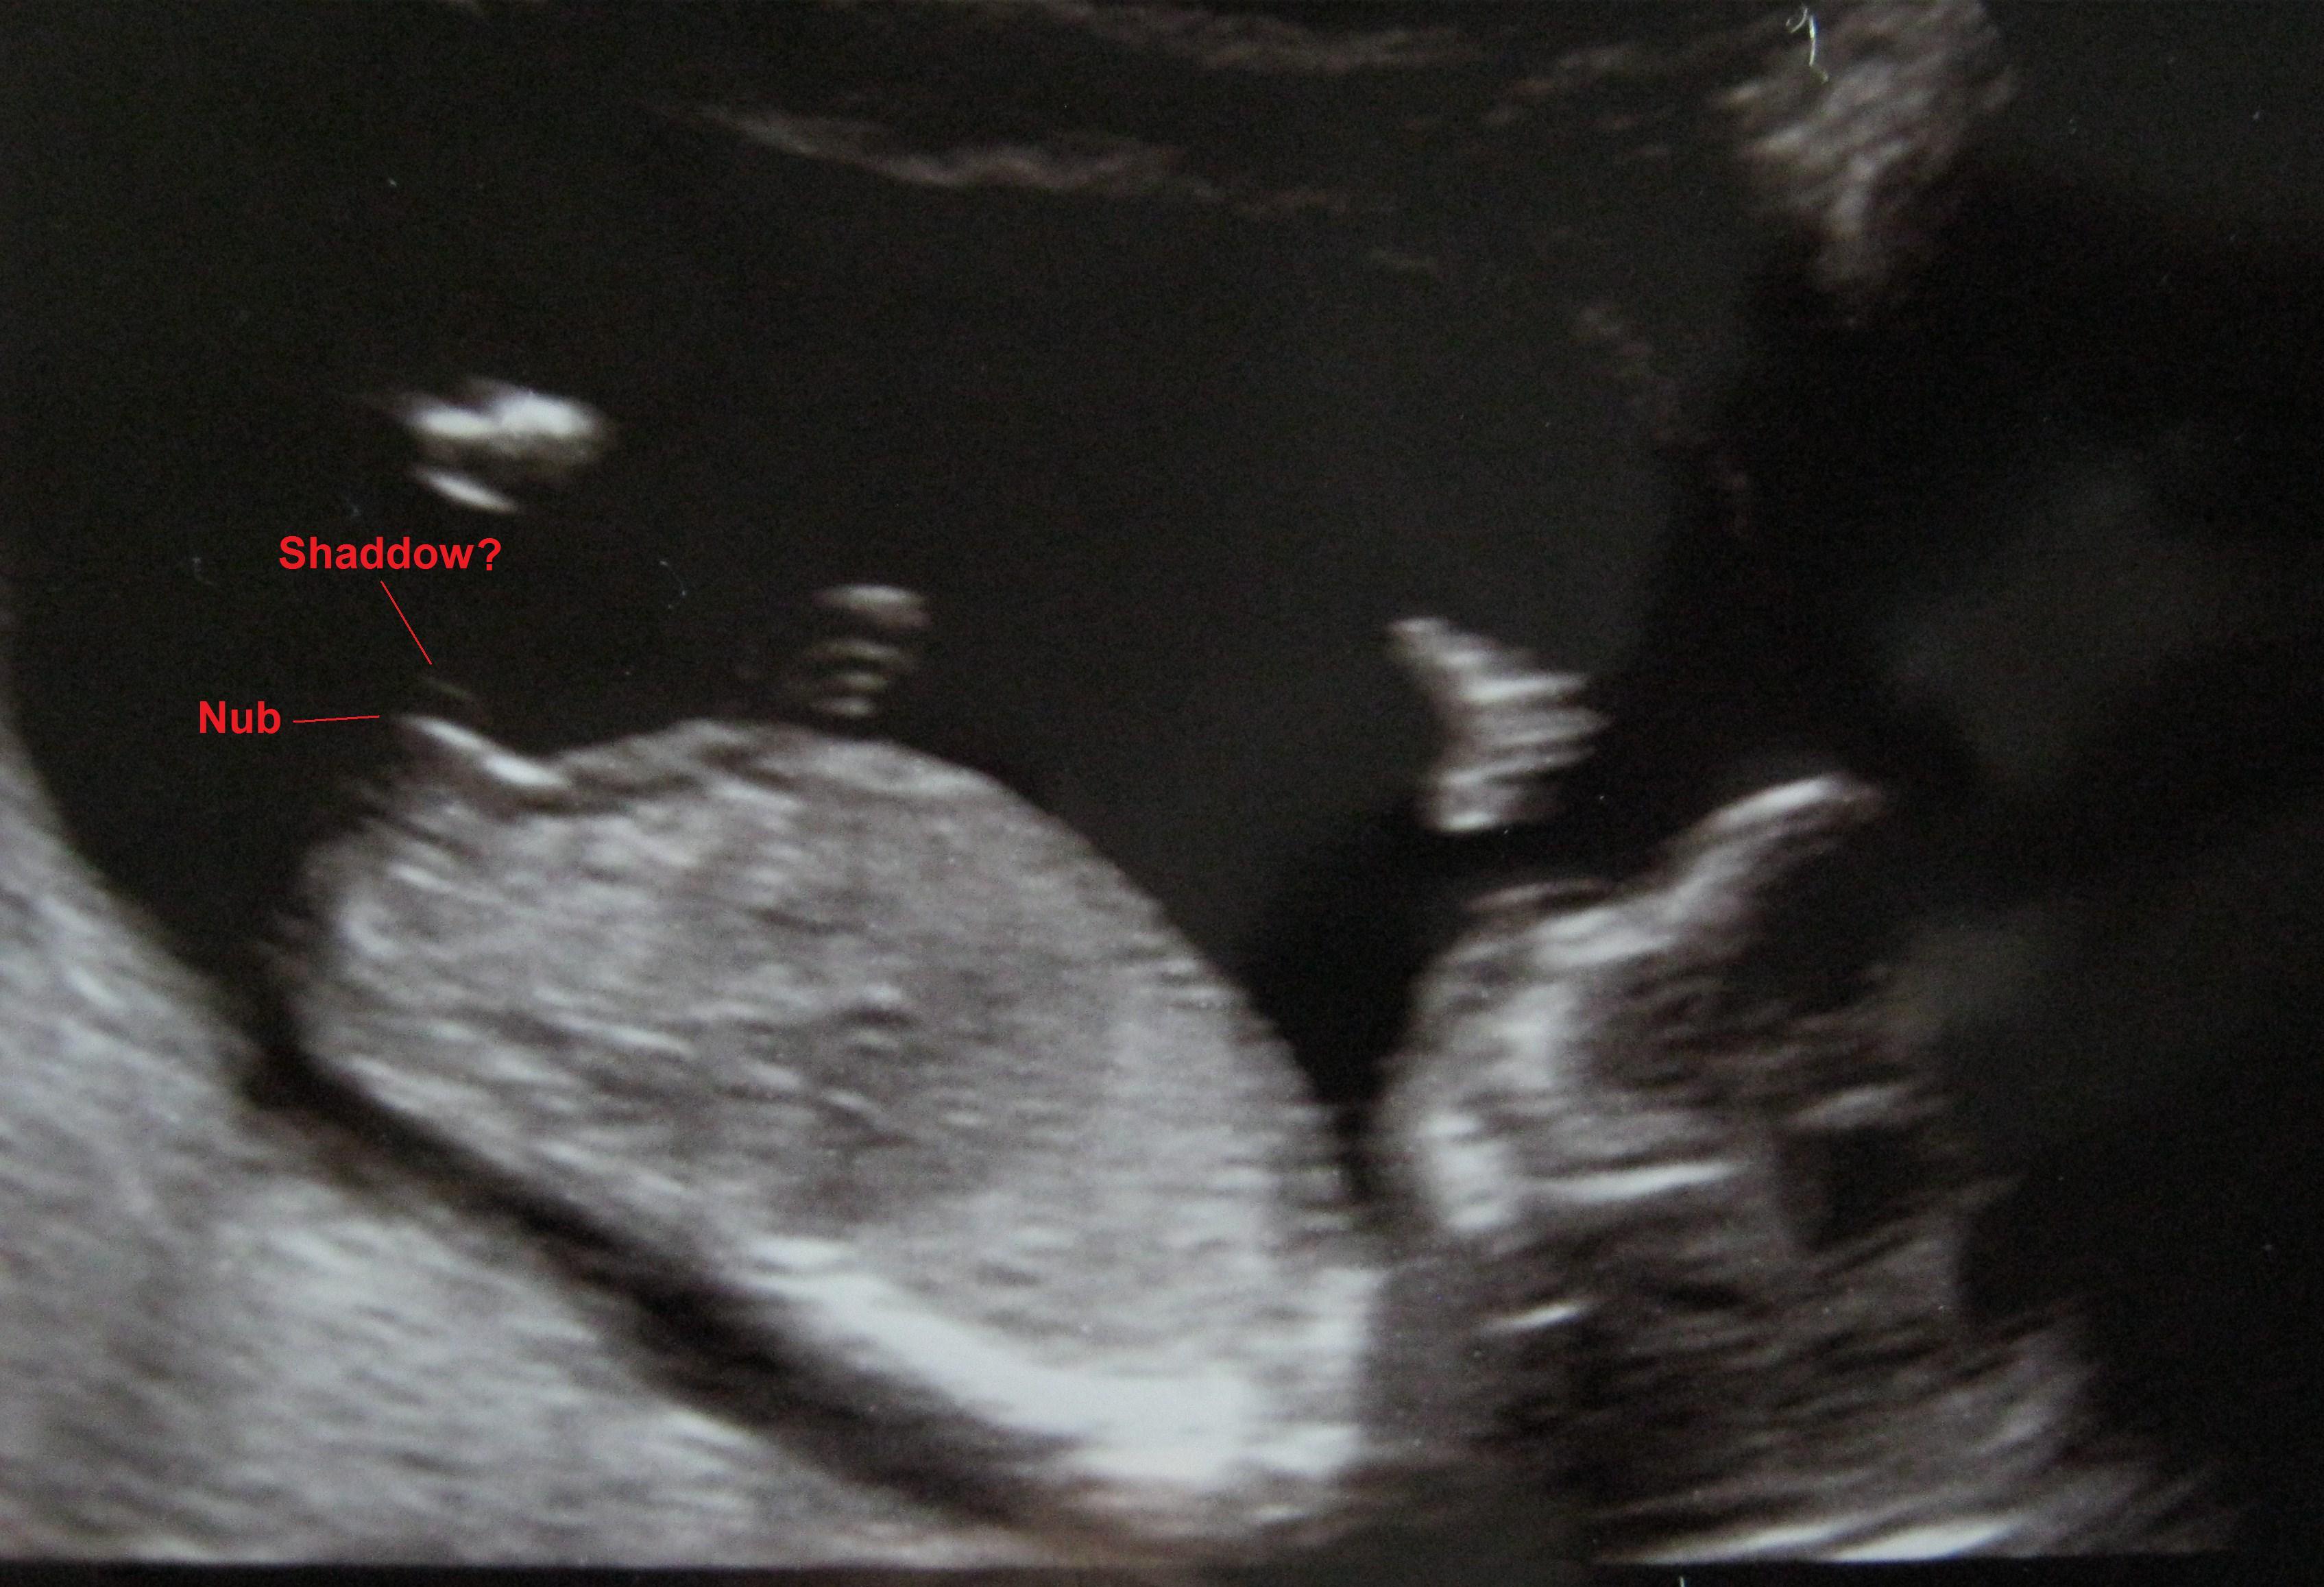

Taking into account the 'shadow' thing that may or may not be part of the nub, please vote :DD: or :DS: